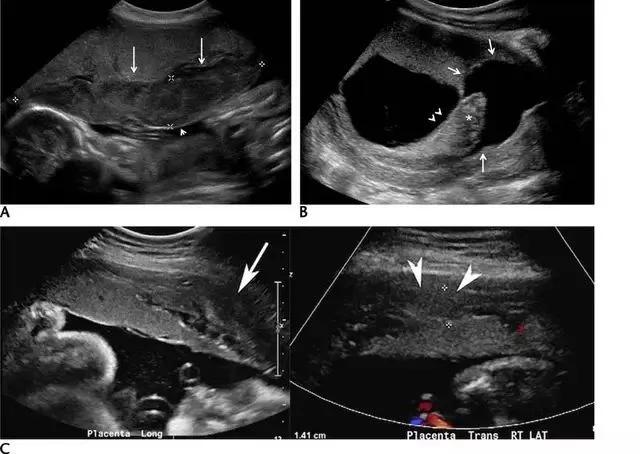

副胎盘是指一个或多个附属胎盘小叶通过血管与主胎盘相连,其发生率在所有妊娠中约占 5%~6%,在高龄孕妇及人工授精时发生率还会高一些。双胎盘是副胎盘的一个变异,其两叶胎盘的大小近似(图 4)。 在超声上,副胎盘表现为两个独立的胎盘通过脐带与主胎盘相连(图 5)

图 5 A 示孕 26 周的胎盘横切面,箭头示 2 个独立的胎盘小叶(长箭头),箭号指示二者之间可见脐带起源于此;图 B 为孕 34 周胎儿死亡后的胎盘大体病理标本,箭头示两个独立的胎盘由源自主胎盘的脐带相连接;该胎儿的死因是由于较大脐膨出导致脐带扭结、脐血管破裂

(4)胎盘间质发育不全是一种极其罕见的胎盘血管畸形,也称为间质干绒毛增生,表现为绒毛膜血管的瘤样扩张、充血及绒毛囊肿或水肿。超声上表现为胎盘增大,内有囊性或葡萄样成分,可类似部分性葡萄胎。鉴别诊断包括双胎妊娠之一胎儿存活并部分性葡萄胎、绒毛膜血管瘤、绒毛膜下或胎盘前出血。最终诊断常需要胎盘病检(图 9)。

图 9 示胎盘间质发育不全:孕妇 27 岁,孕 13 周。A 为胎盘横切面,可见胎盘表面及一侧的簇状囊性结构(长箭头示),小箭头示外观正常的胎儿。B 与 A 为同一胎儿,长箭头示胎盘矢状面上的簇状囊性暗区,内无明显血流信号;孕妇血清甲胎蛋白正常;此时,最容易诊断为双胎之一存活并部分性葡萄胎。由于该存活胎儿无明显异常发现,便采取超声随访、保守治疗,胎儿分娩后胎盘病检证实为胎盘发育不全